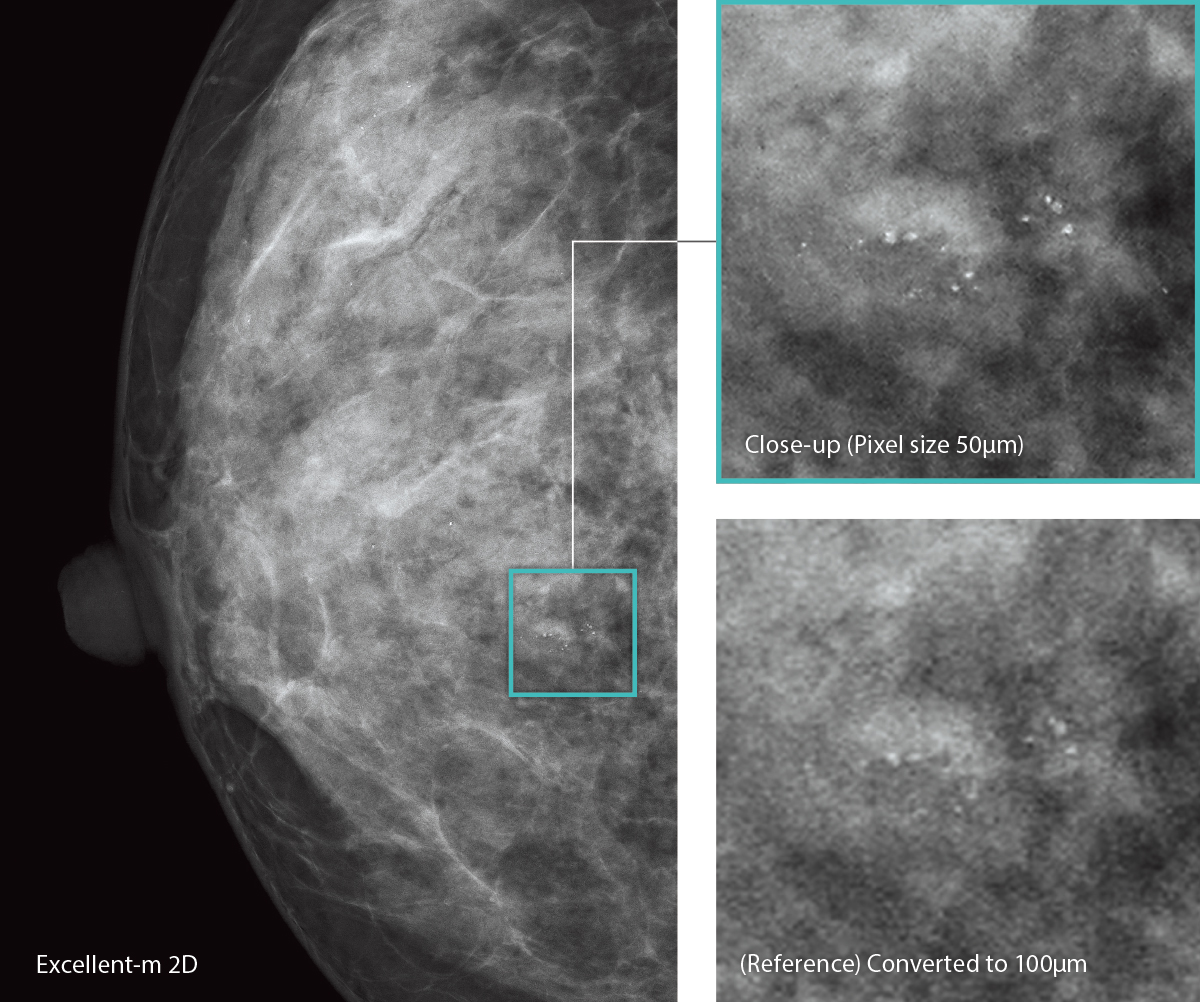

AMULET Innovality utiliza um detector de tela plana de conversão direta feito de selênio amorfo (a-Se) que exibe excelente eficiência de conversão no espectro de raios X mamográficos. O detector HCP (Padrão de fechamento hexagonal) coleta eficientemente sinais elétricos convertidos dos raios X para obter alta resolução e baixo ruído. Este design exclusivo possibilita a realização de uma DQE (Determinação do rendimento quântico) maior do que com a matriz de pixels quadrados de painéis TFT convencionais. Com as informações coletadas pelo detector HCP, a AMULET Innovality cria imagens de alta definição com um tamanho de pixel de 50 μm; o melhor disponível com um detector de conversão direta.